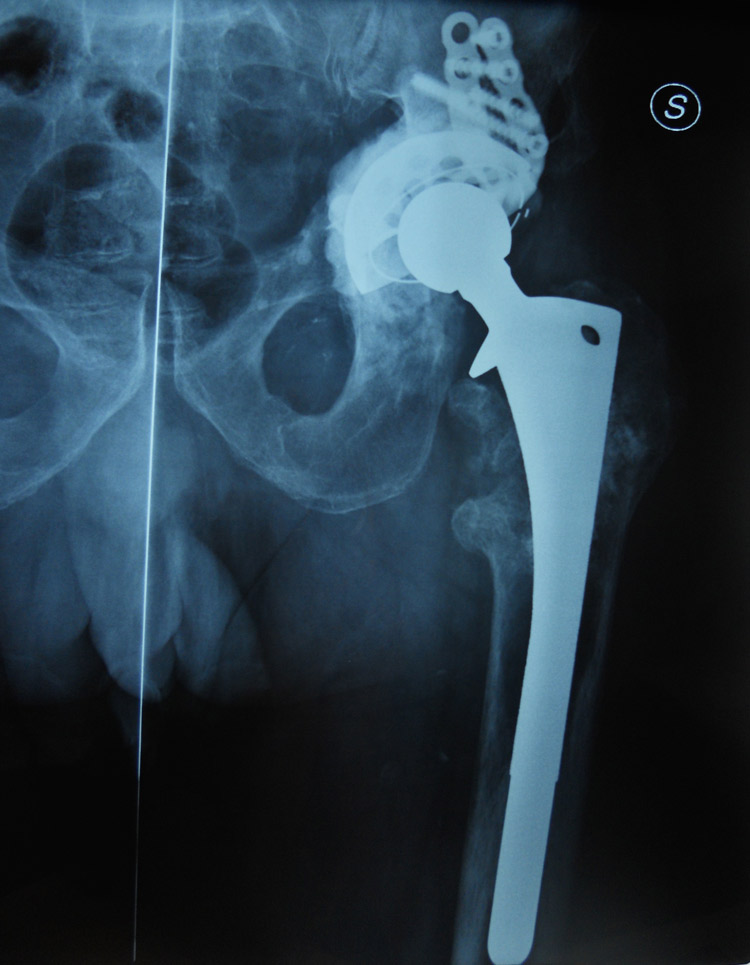

Viene qui presentato un caso di progressiva mobilizzazione del cotile dell’anca sinistra.

Fig. 1 Iniziale mobilizzazione a 2 anni dal primo impianto

Fig. 2 Completa mobilizzazione con rotazione in senso antiorario e migrazione verso l’alto del cotile (frecce) con ampia usura dell’osso del bacino